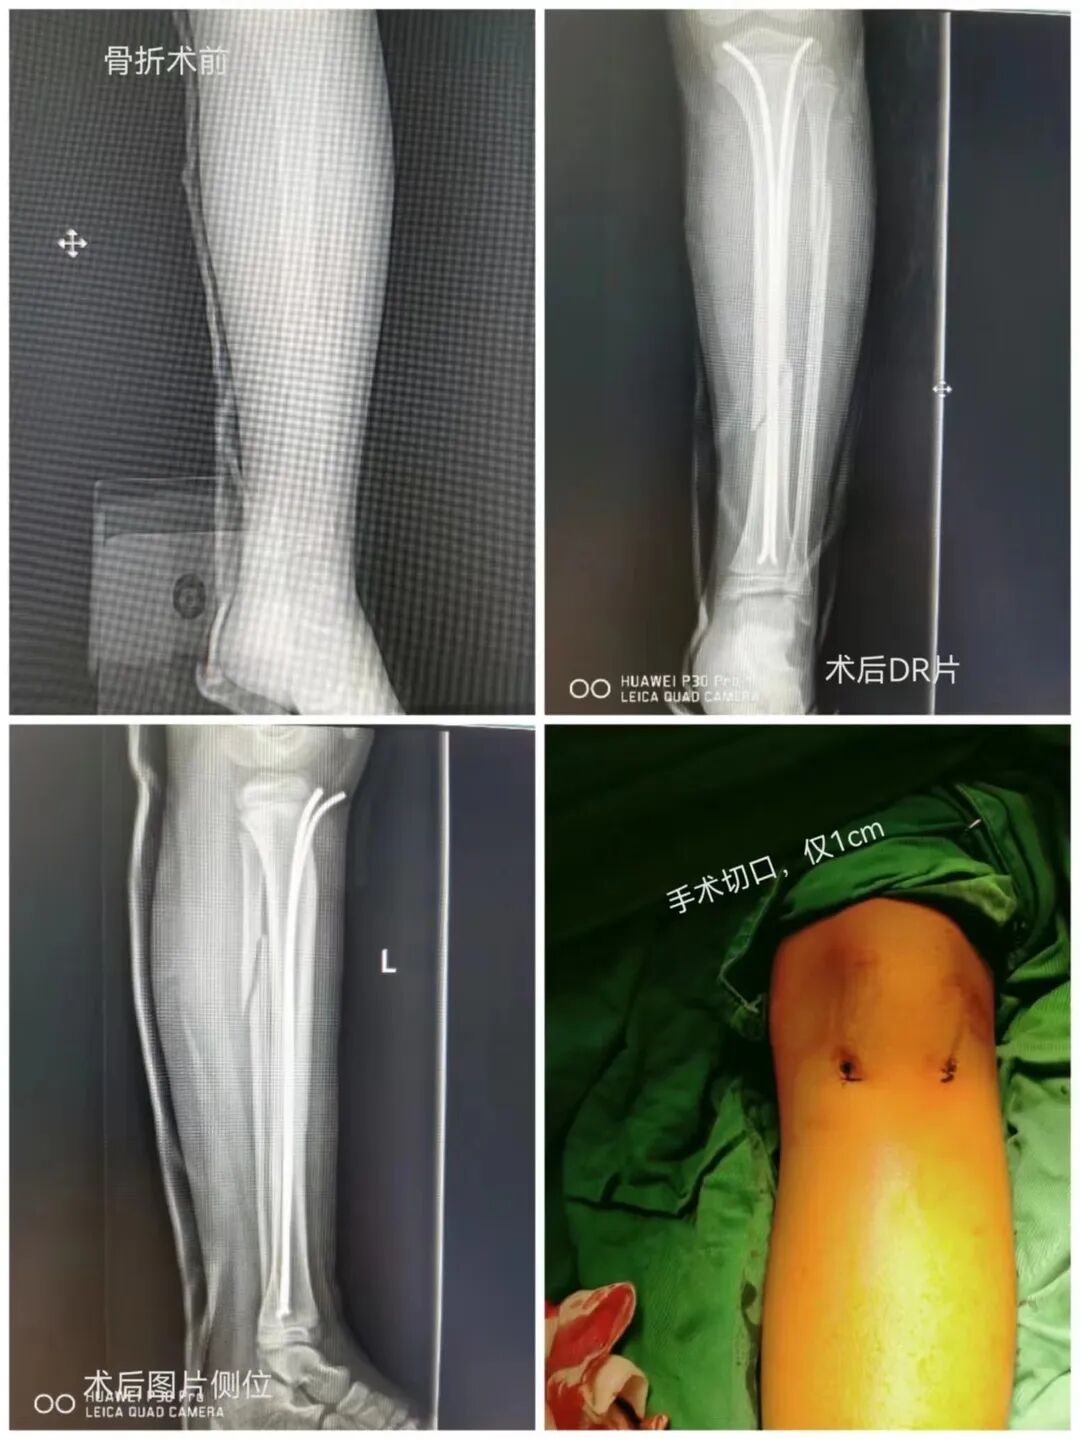

近日,一名9岁男童在玩耍时不慎跌伤,孩子抱着腿哭得撕心裂肺,家长意识到情况的严重性后,立马带着孩子来到我院骨伤科就诊,骨伤科副主任罗斌接诊后仔细查体,初步诊断为左小腿骨折,综合X线片检查结果,建议进行手术治疗。

与家长充分沟通之后,骨伤科创伤团队凭借丰富的手术经验和精湛的操作,患儿在全麻下行手法闭合复位、弹性髓内钉内固定术,手术时间短,创口小,术后恢复快。

弹性髓内钉又名钛合金弹性针。儿童弹性髓内钉技术最早起源于法国,因其创伤小,临床效果佳,所以迅速在世界各地普及。其固定原理是利用钛合金良好的弹性恢复力,将作用于骨的力通过髓腔的3个接触点转换成压力和推力,从而使骨折复位,有足够的力维持骨折的复位位置。